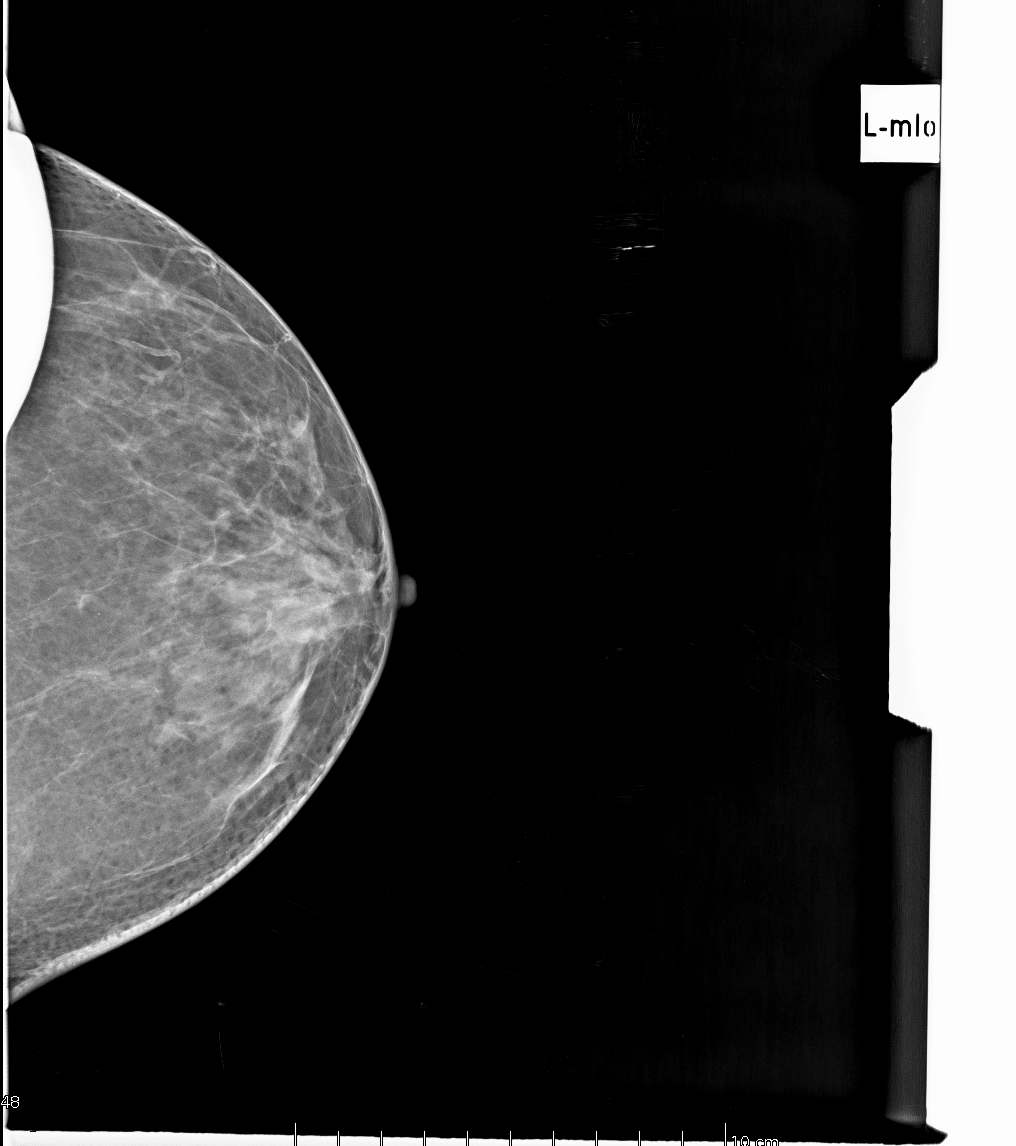

- Системы поддержки принятий решений. Сюда можно включить все вспомогательные сценарии применения, при которых врач пользуется результатами работы ИИ-системы, но самостоятельно принимает все решения. Примеры - подсвечивание сложных областей интереса (например, подозрительных микрокальцинатов на маммографии), чтобы врач не пропустил их при высокой загруженности; оценка дополнительных параметров и автоматизация рутинных измерений (плотность молочной железы, объём кровоизлияния) и многие другие задачи (распознавание голоса и автоматическое заполнение протокола).